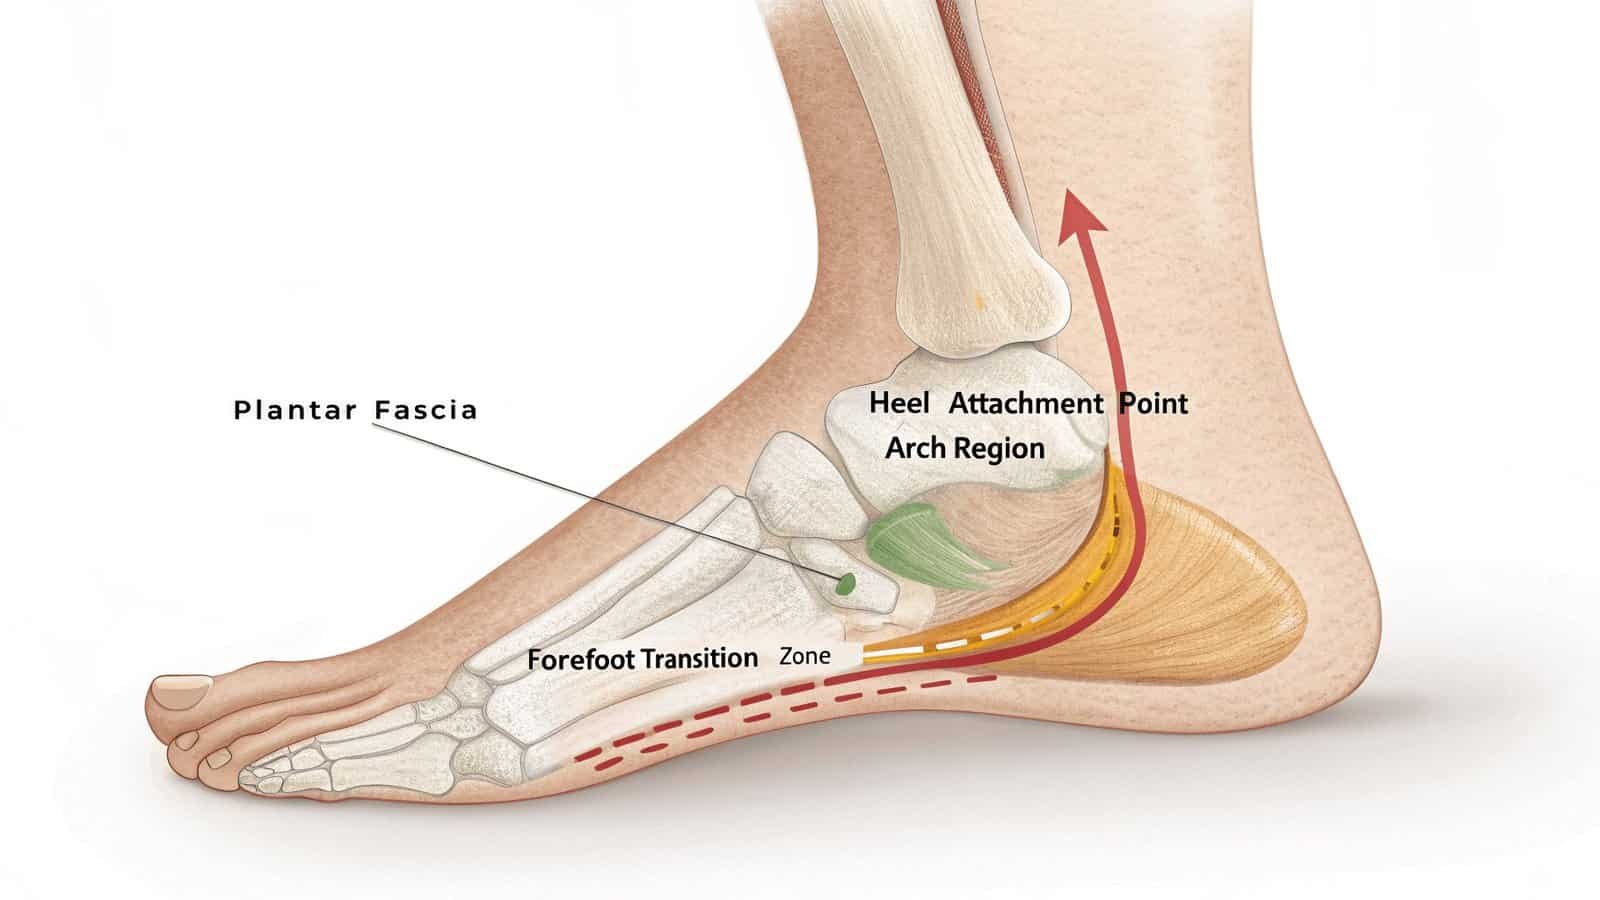

The plantar fascia absorbs shock during movement. Overuse, poor mechanics, or sudden increases in activity strain this tissue, causing microtears and inflammation at its weakest points.

The plantar fascia suffers most at these key locations:

1. Heel Attachment Point

- Bears maximum tension during push-off

2. Arch Region

- Collapsed arches overstretch the fascia

3. Forefoot Transition Zone

- Where fascia fibers fan out